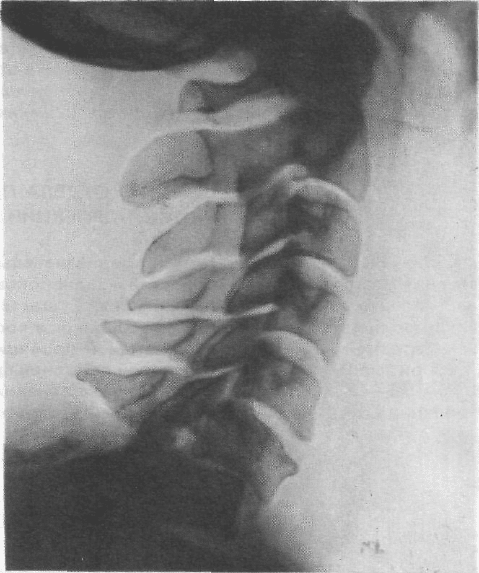

СНИМОК

ШЕЙНОГО ОТДЕЛА ПОЗВОНОЧНИКА

В БОКОВОЙ ПРОЕКЦИИ

• Назначение снимка. Снимок предназначен для изучения шейного

отдела позвоночника на всем протяжении. Однако у больных с короткой

шеей один или два нижних шейных позвонка обычно не выявляются, так как

перекрываются изображением скелета плечевого пояса.

• Укладка больного для выполнения снимка. I вариант. С целью

максимально возможного смещения плечевого пояса книзу оптимальным

положением больного при съемке является вертикальное — стоя или сидя

у стойки с отсеивающей решеткой (рис. 215). В положении стоя для боль-

шего оттягивания плеч книзу целесообразно дать в каждую руку больного

небольшой груз, например мешочки с песком. В положении сидя больной

захватывает кистями сиденье стула и активно оттягивает плечи вниз.

Срединную сагиттальную плоскость головы и тела устанавливают парал-

лельно плоскости стойки. Кассету размером 18X24 см помещают в кассето-

держателе в вертикальном положении, верхний край ее соответствует

верхней части ушной раковины. Вертикальная линия, проведенная от сосце-

видного отростка вниз, соответствует средней линии стойки и кассеты.

Центральный пучок рентгеновского излучения направляют в горизонтальной

плоскости на середину вертикальной линии между верхушкой сосцевидного

отростка и надключичной ямкой.